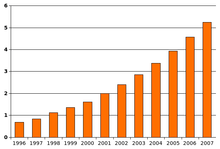

The number of reported cases of autism increased dramatically in the 1990s and early 2000s. This increase is largely attributable to changes in diagnostic practices, referral patterns, availability of services, age at diagnosis, and public awareness,[195][197] though unidentified environmental risk factors cannot be ruled out.[6] The available evidence does not rule out the possibility that autism's true prevalence has increased;[195] a real increase would suggest directing more attention and funding toward changing environmental factors instead of continuing to focus on genetics.[198]